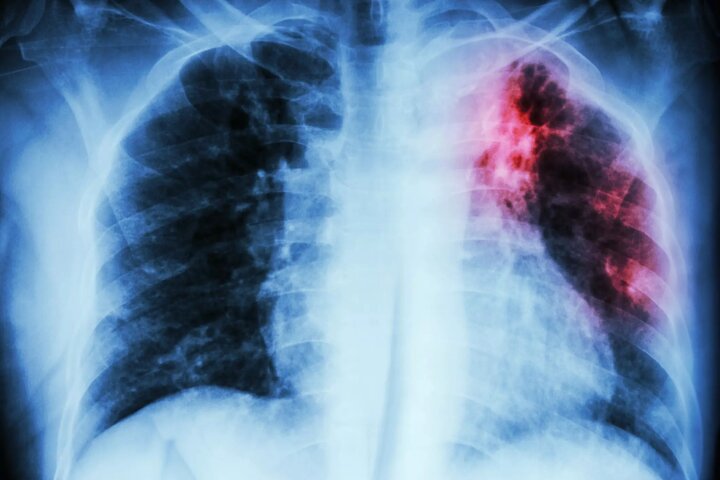

افزایش مبتلایان به یک عفونت کشنده در انگلیس

یزدفردا: آژانس امنیت بهداشتی انگلیس (UKHSA) اخیرا اعلام کرد که موارد ابتلا به سل در نیمه اول سال جاری میلادی (۲۰۲۳) در مقایسه با م ...

مهم ترین عامل ابتلا به سل مشص شد

یزدفردا: رژیم غذایی سالم میتواند عفونتهای ناشی از بیماری سل را تا ۵۰ درصد کاهش دهد. ...